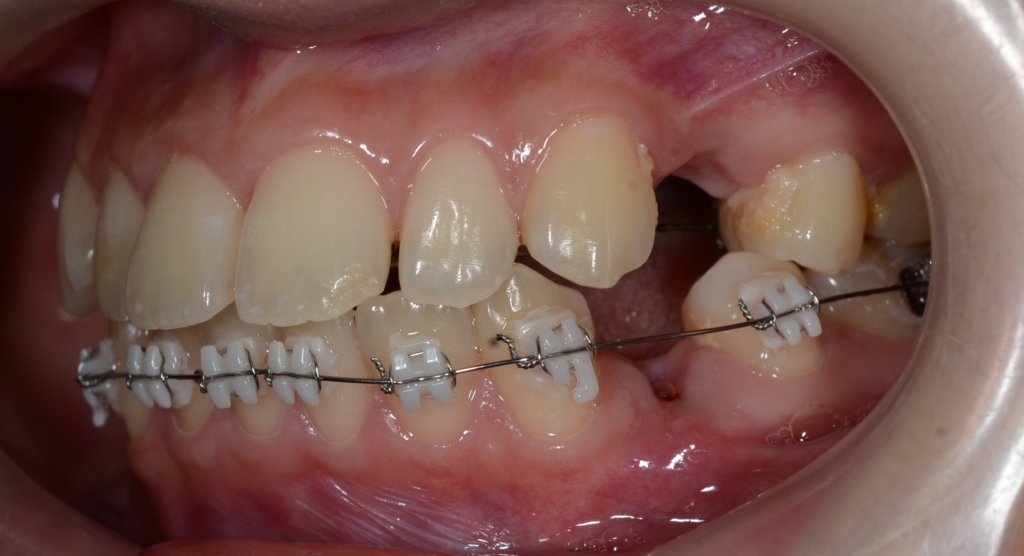

ついでに、歯並びの比較です

上段が矯正治療前、下段が矯正治療後